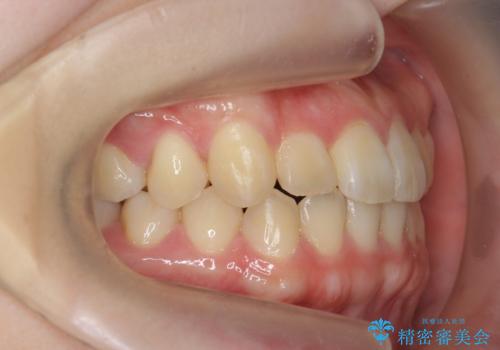

前歯のねじれを改善 小矯正+マウスピース矯正インビザライン

- 「前歯のねじれ、見た目を改善したい。」と矯正治療を希望され来院されました。

マウスピース矯正では改善の難しい前歯のねじれを前歯の部分ワイヤー矯正で改善したのち、インビザライン矯正を行い歯列を整えます。

インビザラインを行う前に前歯の部分矯正を行ったことで、しっかりとねじれが取れ整った歯列へと仕上げることが出来ました。